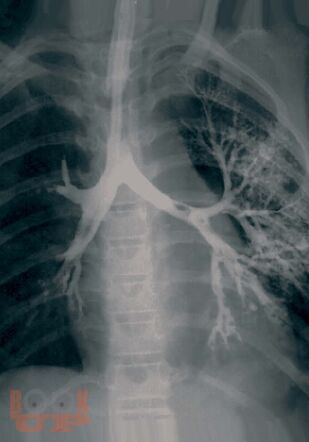

В монографии представлены важнейшие хронические заболевания легких у детей, рассмотрены вопросы терминологии и классификации этих болезней. Описаны клинические проявления различных форм хронической бронхолегочной патологии, даны критерии и современные методы диагностики. Отдельные главы посвящены хроническим воспалительным заболеваниям легких, врожденной и наследственной патологии, бронхиальной астме, интерстициальным болезням легких, грибковым поражениям бронхолегочной системы. Рассмотрены особенности течения туберкулеза при хронических неспецифических заболеваниях легких. Изложены принципы терапии хронических заболеваний легких у детей. Книга адресована педиатрам, пульмонологам, аллергологам, врачам общей практики, сотрудникам научно-исследовательских учреждений и учебных заведений.